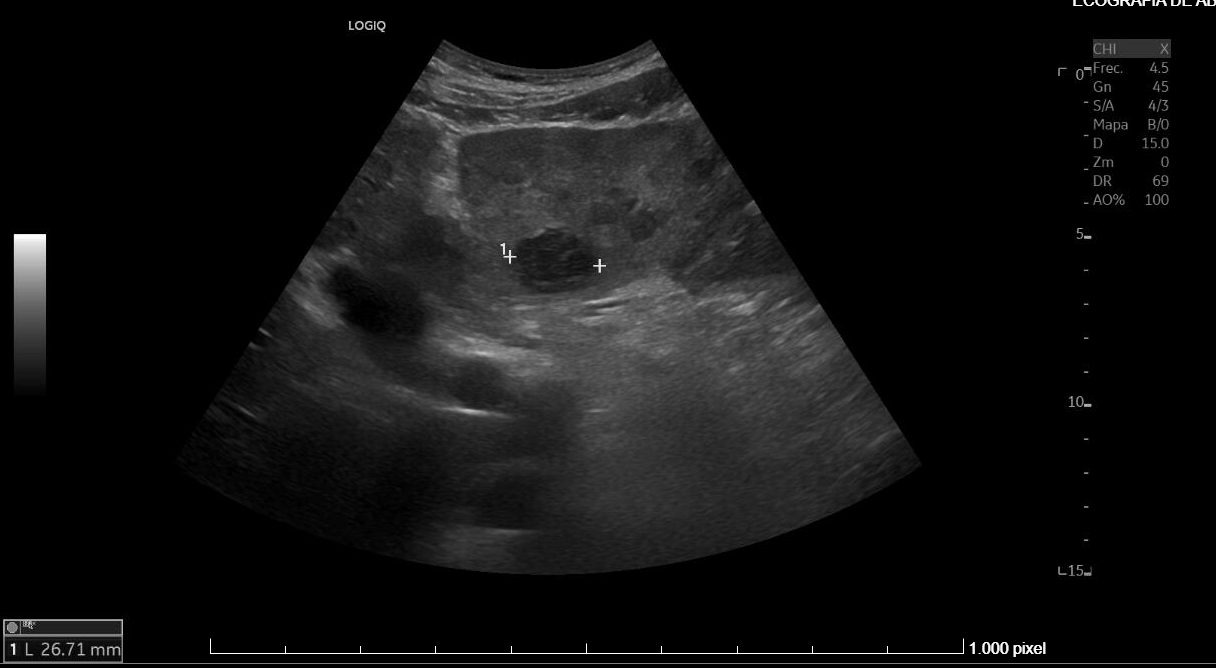

Diagnostico diferencial: Fasciolasis Hepatica, hidatidosis hepatica, Etiología metastasica.

Juicio clínico: Síndrome febril agudo en contexto de infección hepatica probable por Fasciola Hepatica . Esplenomegalia y trombocitopenia.